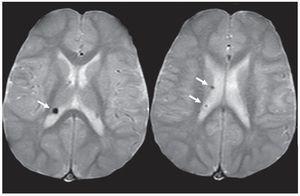

Su tamaño es variable. Mientras las pequeñas son lesiones de tipo puntiforme, hiperintensas en ponderación T2 y FLAIR, las grandes presentan diversos aspectos: pueden ser lineales, tener forma de cuñas o integrar un conglomerado. Sin embargo, la presentación más habitual es el patrón lineal, que se extiende desde la región periventricular hasta la corteza y se denomina «líneas de migración radial».

En la TC pueden ser levemente hipodensas y también suelen calcificarse (fig. 6), mientras que en la RM se identifican como imágenes hiperintensas en ponderación T2 y FLAIR (figs. 7 y 8). Rara vez realzan poscontraste.

Figura 7. Líneas de migración radial. Secuencia FLAIR donde se observa, a nivel de la sustancia blanca periventricular adyacente a la prolongación occipital del ventrículo lateral izquierdo, una línea hiperintensa que se extiende hacia la corteza (flechas rectas). También se presentan quistes parenquimatosos (flechas curvas). Ambos hallazgos son característicos de esclerosis tuberosa.

Figura 8. Lesión de sustancia blanca. En la secuencia FLAIR se nota una banda gruesa hiperintensa que se extiende desde la sustancia blanca periventricular hasta la corteza (flechas).